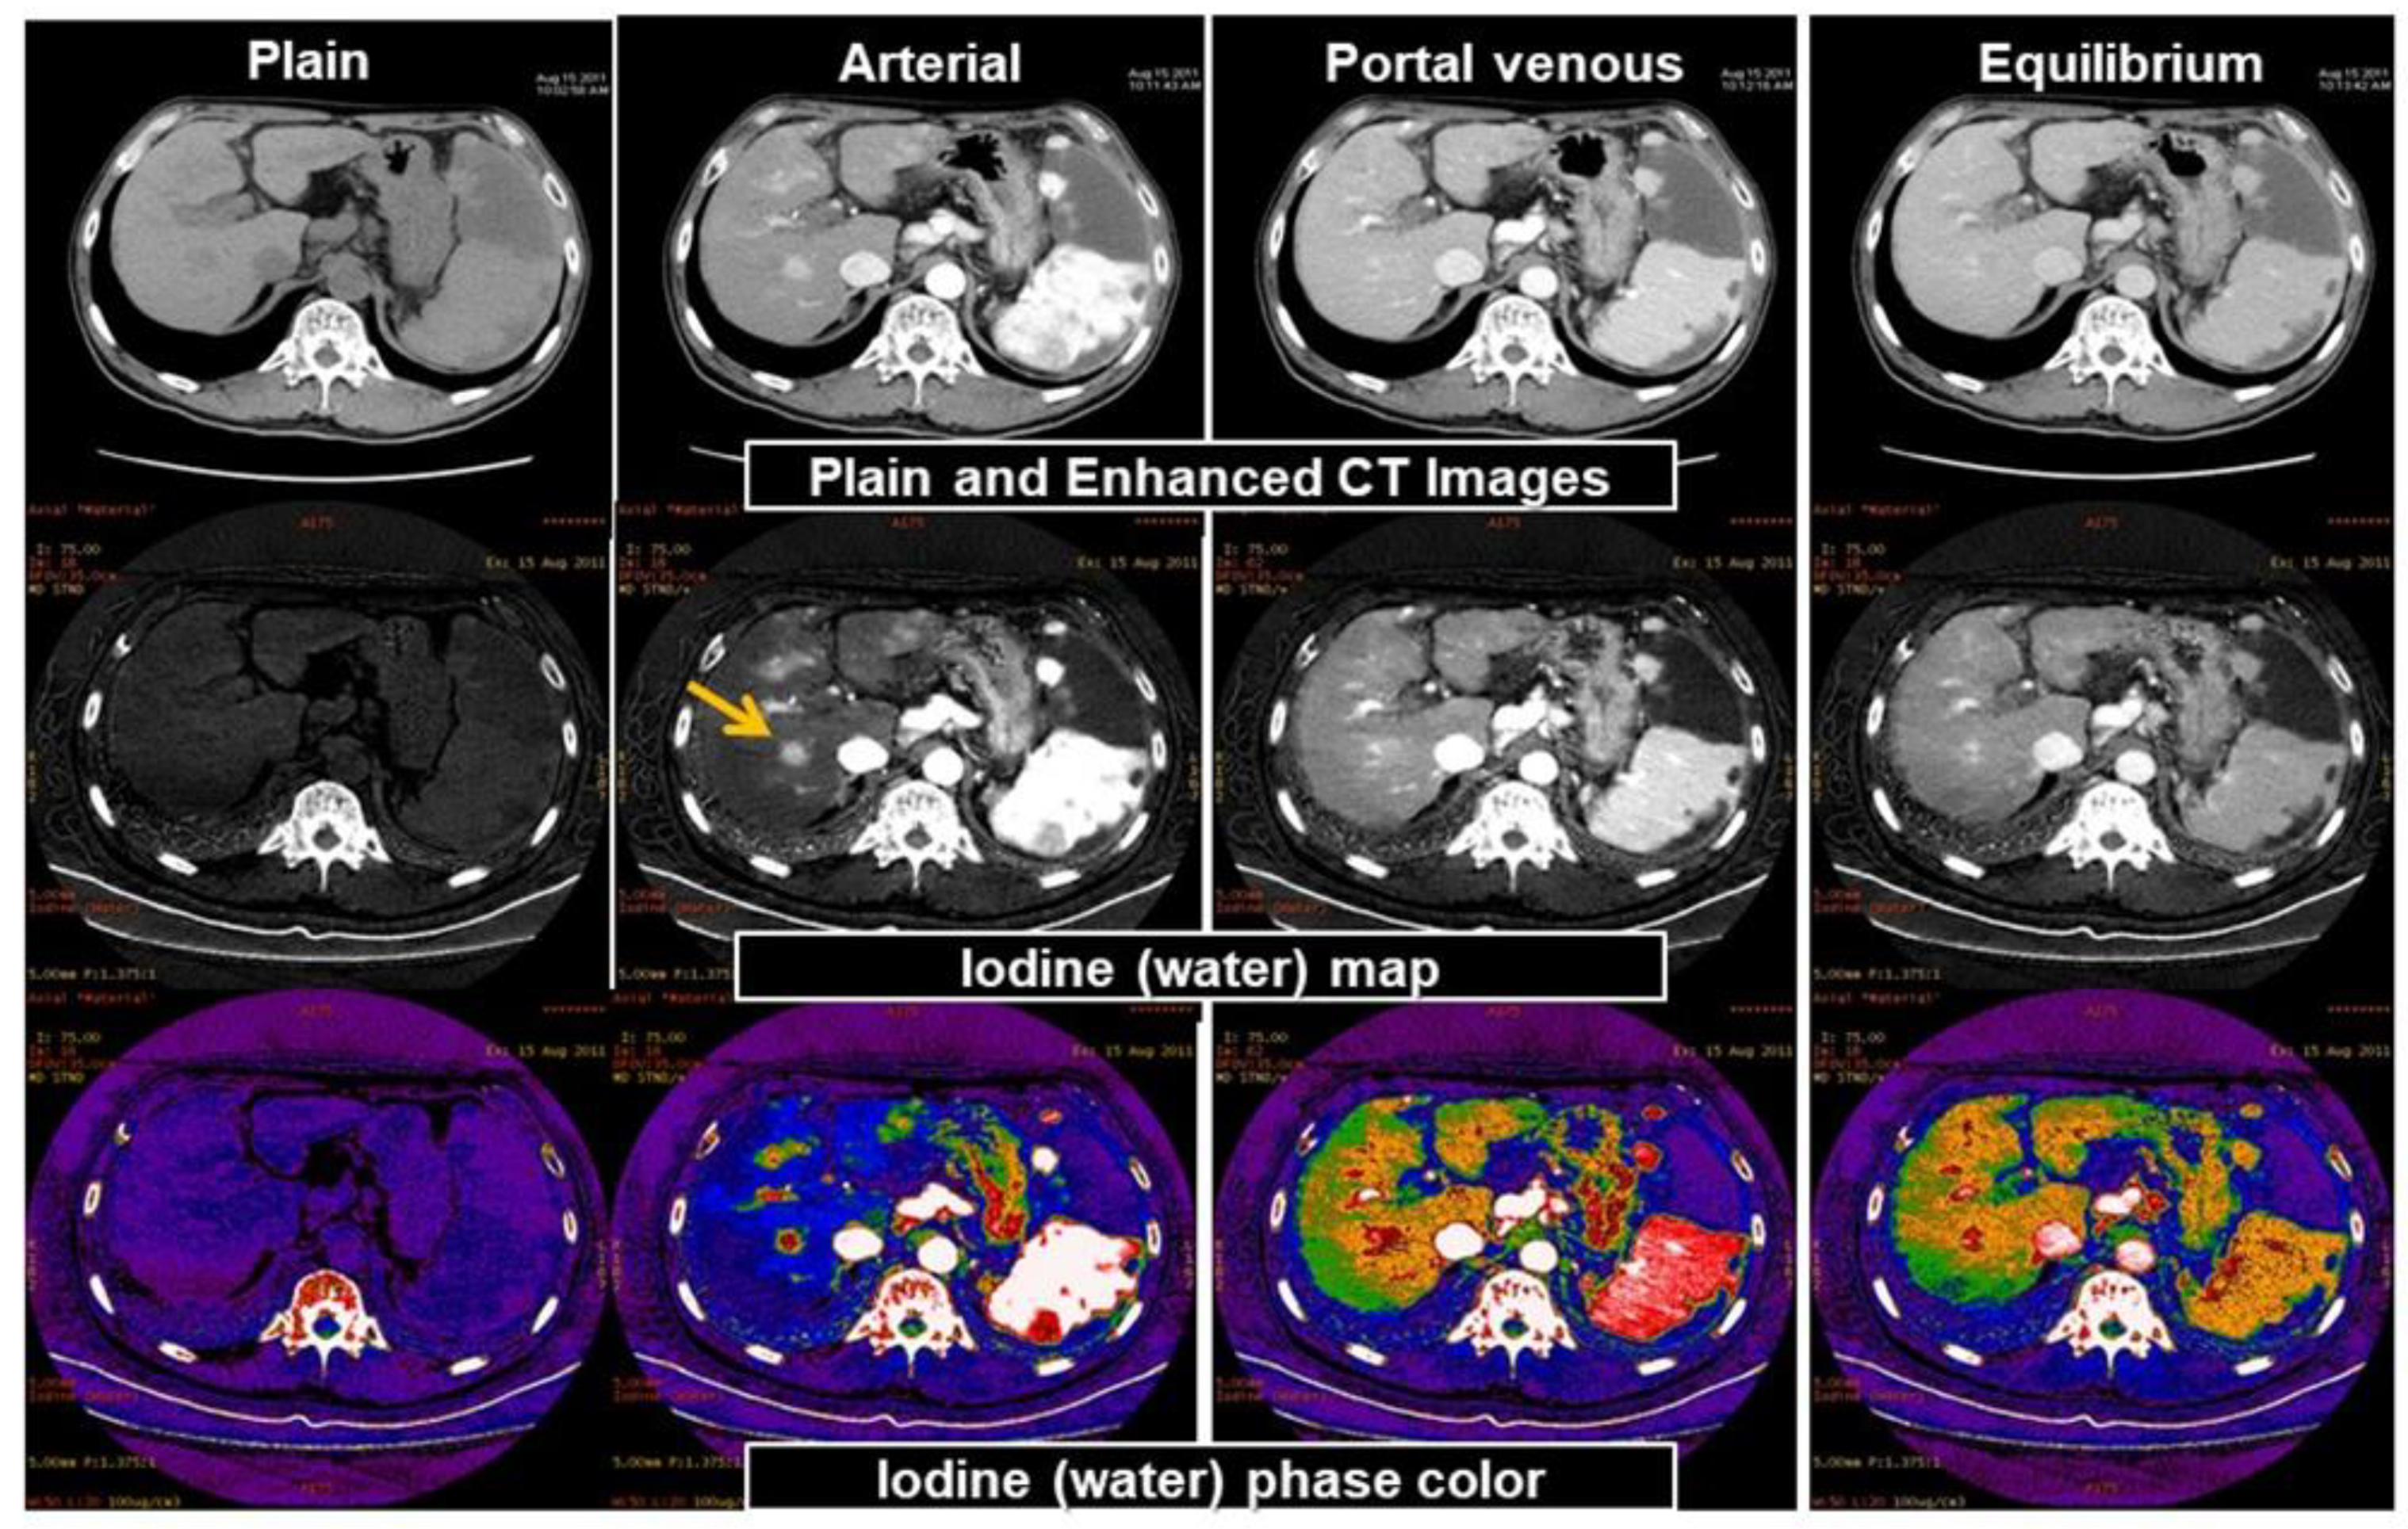

3.2. Material Decomposition

3.3. Virtual Unenhanced CT